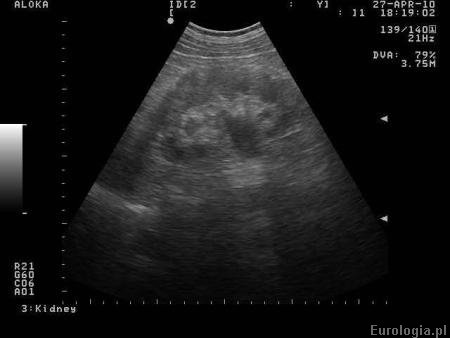

Wodonercze rozpoznawane jest na podstawie badań obrazowych. Badanie USG jamy brzusznej jest podstawowym badaniem obrazowym w diagnostyce wodonercza. W badaniu USG określany jest stopień zastoju moczu w UKM - wymiar przednio - tylny miedniczki i grubość warstwy miąższowej - kory nerki. Do obrazowania wodonercza oprócz ultrasonografii wykorzystuje się także tomografię komputerową, urografię i rezonans magnetyczny. Scyntygrafia jest badaniem, które pozwala ocenić czynność nerki. W czasie badania pacjent otrzymuje dożylnie radioaktywny znacznik a następnie ocenia się szybkość jego wydalania przez nerki.

Fot. Wodonercze - obraz w USG